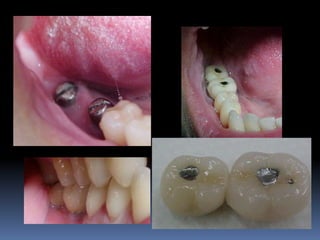

Altura interoclusal

Aumento de coroa clínica

Espaço interproximal modificado

Plataformas regulares ou plataformas

largas?

Estética durante seleção de pilares

Má posição do implante

Risco biomecânico

Perdas e fraturas